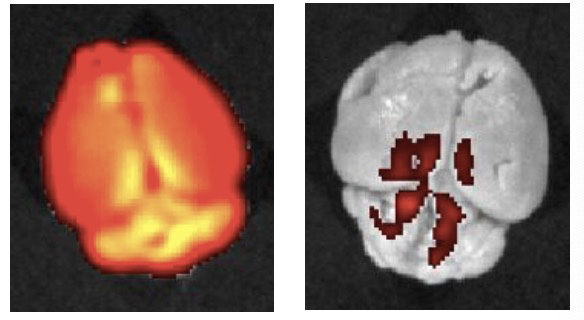

他认为,上述脑部疾病尚无有效的临床药物,其主要难点在于绝大多数小分子药物无法穿透血脑屏障,也就是上述的无法通过大脑的“卫兵”,作用于大脑发病区域。现在,修饰过的纳米药物相当于一种“精准快递”,直接作用于血脑屏障,并激活其自身的清除机制,去清除脑内的物理病灶。

“从影像学角度来看,物理病灶几乎都被去掉了,但是能否改善认知,并应用于临床,还有很长的路要走。”田肖和表示,下一步他们将积极为申请预临床试验做准备。

▲ 大脑血管局部放大图显示,红色的模式药物被递送到大脑里